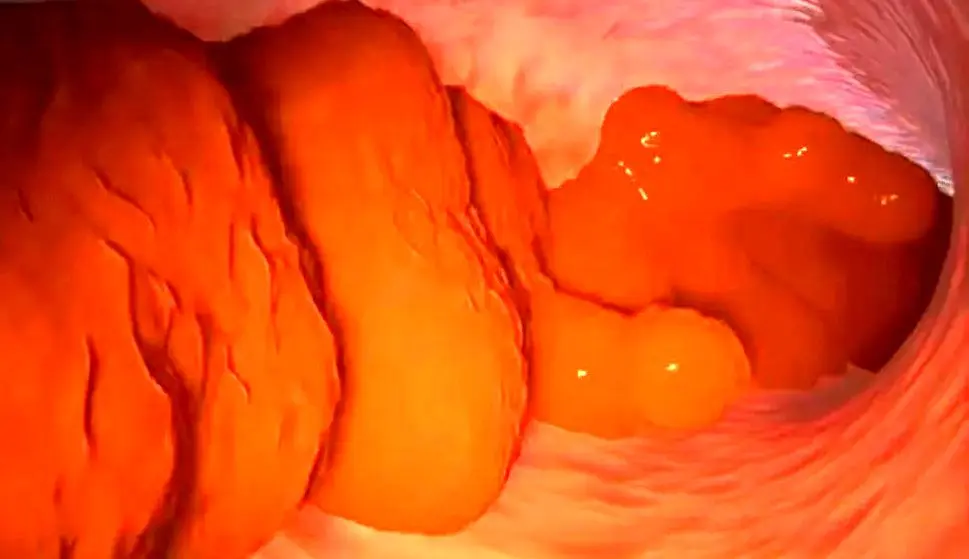

احساس نفخ به مدت سه هفته همراه با کاهش وزن، توده یا تورم در شکم یا خون در مدفوع نیز باید جدی گرفته شود، زیرا ممکن است علائم سرطان باشد. یکی از ساده‌ترین راه‌ها برای چک کردن روده تان آن است که عادات دستشویی خود را ارزیابی کرده و پس از دفع مدفوع آن را بررسی نمایید. آن چه در بررسی مدفوع تان اهمیت دارد ثبات، رنگ و اندازه آن است و اگر دچار تغییر شده باشد باید به پزشک مراجعه کنید. مدفوع سالم مانند یک سوسیس نرم و صاف است. از نظر تعداد دفعه اجابت مزاج معمولا سه بار در روز طبیعی می‌باشد. اکثر افراد هنگام صبح دستشویی می‌روند، اما معمولا زمان درست یا نادرستی برای اجابت مزاج وجود ندارد هر زمانی که نیاز به آن داشتید باید به دستشویی بروید!

اندازه مدفوع نیز مهم است. به گفته پزشکان مدفوع بزرگ‌تر (به اندازه دو یا چند تخم مرغ بزرگ) با خطر کمتر سرطان روده بزرگ نوعی سرطان روده، مرتبط است. رنگ مدفوع باید قهوه‌ای باشد و در صورت وجود خون در آن باید به پزشک عمومی مراجعه کرد، زیرا می‌تواند نشانه بروز سرطان روده باشد. علائم مهم دیگر تغییر در بافت مدفوع است که پیش‌تر برای تان معمول نبوده مانند بروز اسهال یا یبوست و هم چنین تغییر در عادات توالت کردن مانند نیاز به کم‌تر و بیش‌تر رفتن به دستشویی، درد شکم نفخ، کاهش وزن و خستگی. اگر به مدت سه هفته یا بیش‌تر چنین علائمی داشتید به پزشک عمومی خود مراجعه کرده و در این باره خجالت نکشید.